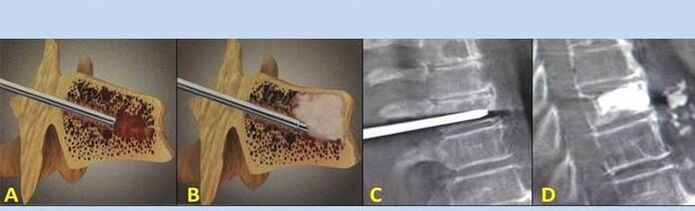

- Nucleoplastie – îndepărtarea miezului discului intervertebral. Operația ameliorează presiunea asupra terminațiilor nervoase.

- Vertebroplastie prin puncție – metoda de stabilizare a vertebrelor. În timpul procedurii, medicul umple cavitățile coloanei vertebrale cu ciment osos.